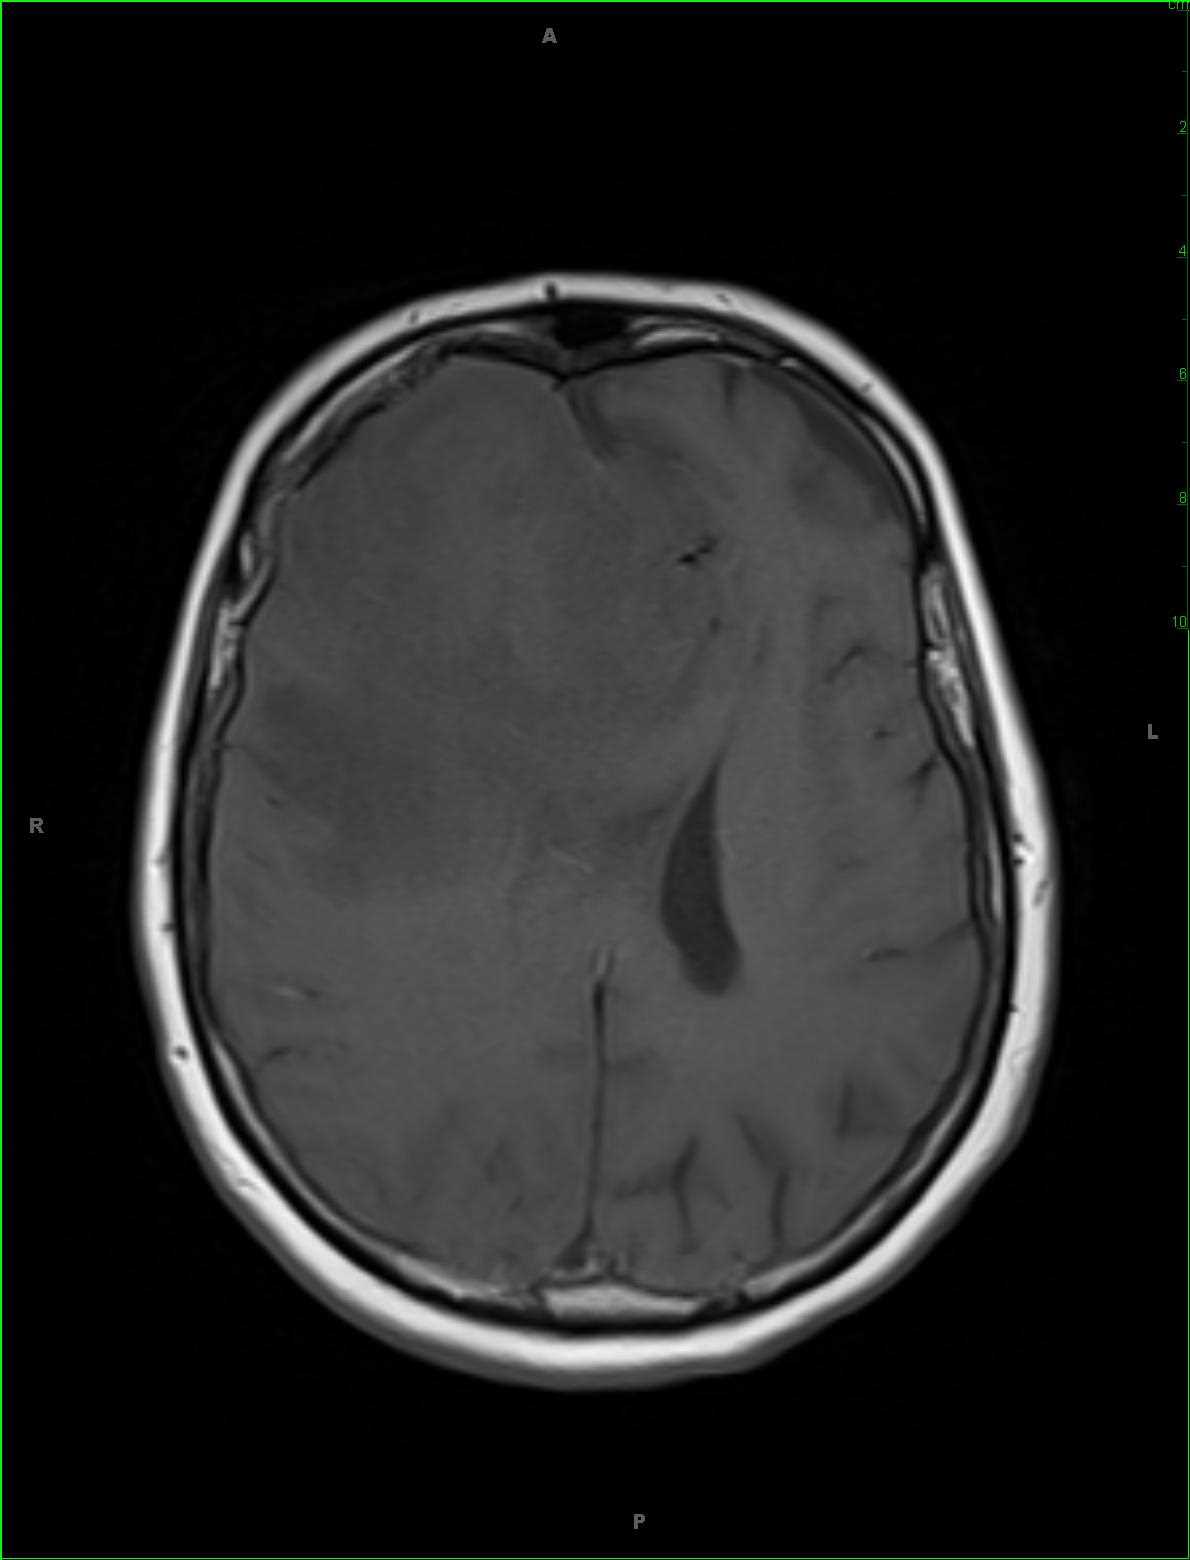

48-year-old female who attempted suicide by overdosing on acetaminophen. There is hyperintense FLAIR signal abnormality within the dorsomedial aspect of the thalami and extending into the midbrain. There is abnormal diffusion restriction at the sites without contrast enhancement. Given the stated clinical history, the findings are most compatible with acute hepatic encephalopathy in the setting of acetaminophen toxicity. Hepatic encephalopathy may be either acute or chronic. Acute cases typically arise in the setting of acute hepatic failure, such as in this case. Chronic cases tend to occur in patients who undergone prior portosystemic bypass without associated intrinsic hepatocellular disease or in patients with hepatocellular dysfunction and portosystemic shunting. Classic MR imaging abnormalities include high T1 signal intensity within the globus pallidus with mild cases demonstrating T2 FLAIR symmetrically hyperintense signal in the insula, thalami, and posterior limbs of the internal capsules. Diffusion signal abnormality may be present and can reverse if therapy for the underlying acute decompensation is instituted early. The extent and severity of the FLAIR and diffusion-weighted imaging correlates with the plasma ammonia level.